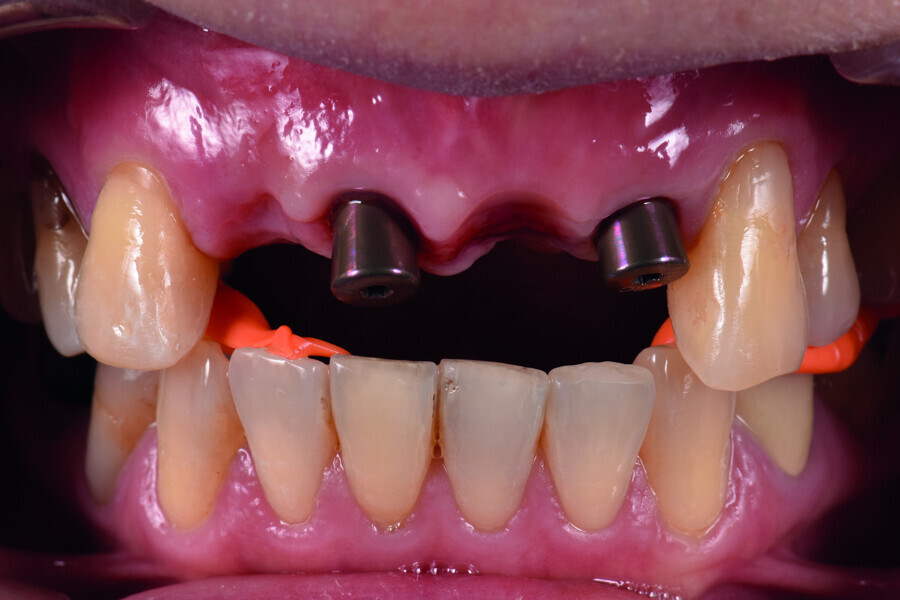

Fig. 15: Insertion of provisional abutments.